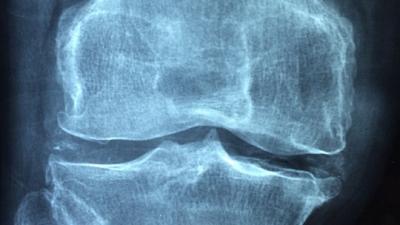

Digitale diagnosetools moeten het mogelijk maken om patiënten met spier- en gewrichtsklachten beter te diagnosticeren, zodat zij sneller de juiste behandeling